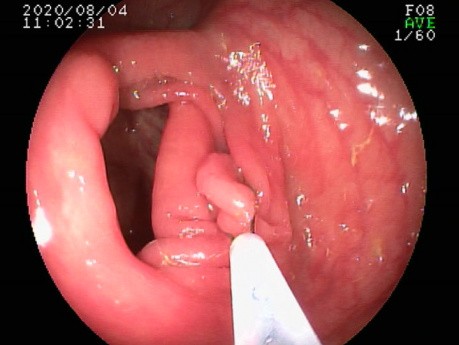

Resekcja polipa odbytnicy przy użyciu pętli "na...

W filmie pokazano resekcję polipa siedzącego odbytnicy o średnicy 7 mm przy użyciu pętli "na zimno" Exacto.